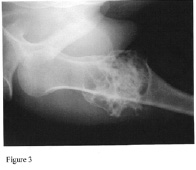

Pelvic Girdle (Hips and Pelvis) |

Osteochondromas of the proximal femur (Figure 3) may lead to progressive hip dysplasia. There have been reported cases of acetabular dysplasia with subluxation of the hip in patients with MHE. This results from exostoses located within or about the acetabulum that may interfere with normal articulation.